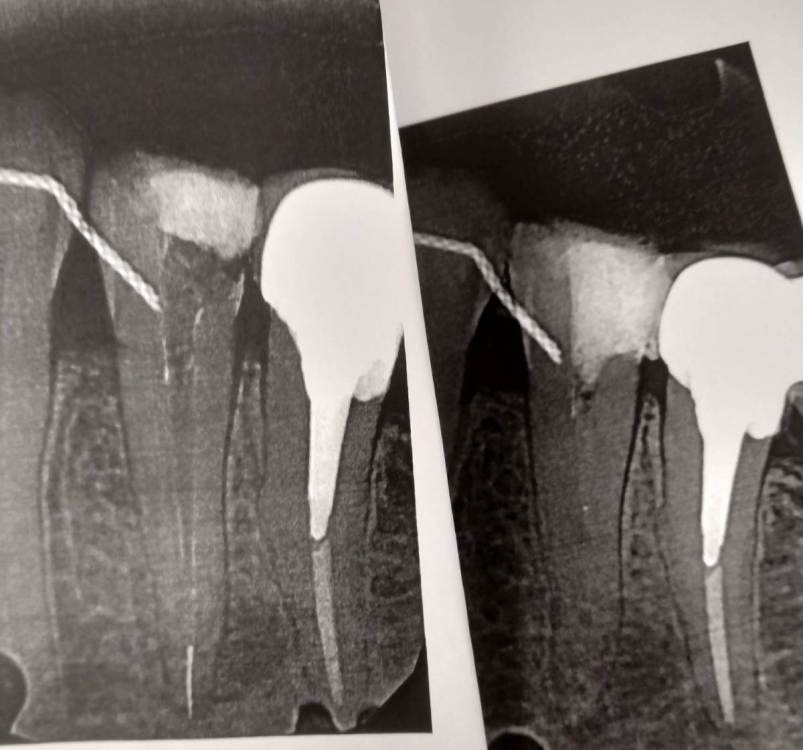

Ico Опубликовано 10 апреля, 2022 Автор Поделиться Опубликовано 10 апреля, 2022 (изменено) 3 отдельных канала в нижнем премоляре,паковка похожая как у Томаса Ланга.Каллибровка,паковка апексов была по S2 протейперу + 25 к. Изменено 10 апреля, 2022 пользователем Ico 1 1 2 Ссылка на комментарий